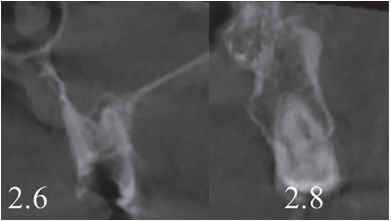

In the radiograph examination, through a panoramic radiograph, both lower third molars were seen retained in horizontal position (Figure 3), and apical radiolucent images in positions of 2.6 and 4.6. The cone beam scan evaluated the root morphology of the left upper third molar and the size of the apical radiolucent lesion of the left upper first molar (Figure 4), necessary data to assess the degree of adaptation of the donor tooth in the recipient bed.

The extraction of 4.6 and 2.6 and the curettage of the apical processes were planned, and the autotransplant of the left upper third molar (2.8) to sustain the 2.6 (Figure 5) was suggested to the patient.

associated with the root remains of 2.6 and the conical root of 2.8 are seen.